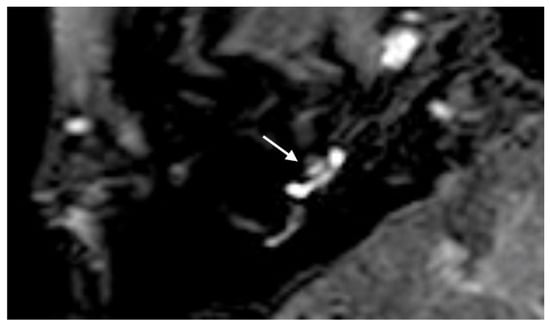

A 66-year-old male was referred to our emergency unit because he developed a sudden hearing loss on the right side without vertigo or tinnitus. He had already had a sudden hearing loss in history on the ipsilateral side, which was recovered. The audiogram revealed a decreased hearing threshold with a PTA of 92.1 dB on the right side. Intraoperatively, the round niche inspection was interpreted as a PLF, and CTP testing was also positive. The contrast enhancement was seen in the right vestibulum and cochlea with 4 h delayed 3D-FLAIR sequences (Figure 6).

Figure 6. A 66-year-old male with a sudden hearing loss on the right side without vertigo or tinnitus. The contrast enhancement was seen in the right vestibulum and cochlea (array) with axial 4 h delayed 3D-FLAIR sequences.